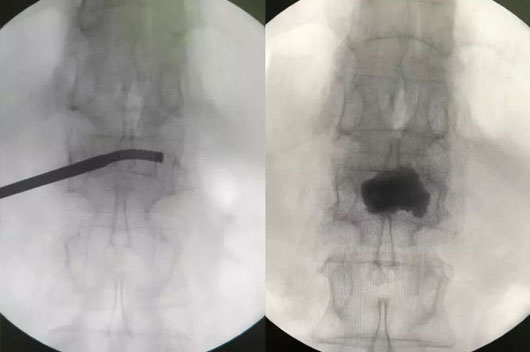

´Ë´ÎÊÖÊõʹÓûúеÈËÍýÏëµ¥²à´©´ÌÑü1×ó²àõè¾¶£¬Çпª0.5cmƤ·ô£¬ÔÚ»úе±ÛÖ¸µ¼Ï¾«×¼ÖÃÈëµ¼Õ롢ͨµÀÖÁ×µÌåÄڵİÐλÖ㬰²ÅÅ¿ÉÍäÇúÇòÄÒ¾ÙÐж¨µãÀ©ÕÅÅòÕÍ£¬Ë³ËìÍê³É¿ÉÍäÇúµ¥²àPKPÊÖÊõ£¨Í¼1-4£©¡£

ͼ1£¬ÖìÔýÌÊÚÖ¸µ¼Íê³É´©´Ìõè¾¶ÍýÏë

ͼ2£¬»úеÈ˸¨ÖúÏÂÖÃÈëµ¼Õë

ͼ3£¬ÍÆ×¢¹ÇË®Äà

ͼ4£¬µ¥²à´©´ÌÖÁ×µÌå¶Ô²à½¨É軡ÐÎͨµÀ£¬¹ÇË®ÄàÂþÑÜÓÅÒì